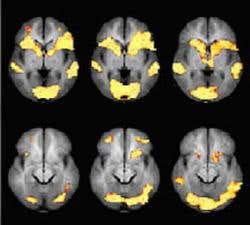

A polygraph test proved unsatisfactory: every time Marie’s name was mentioned Donna’s responses went sky-high. But when Donna approached Cephos of Tyngsboro, Massachusetts, for an fMRI scan, which picks up changes in blood flow and oxygenation in the brain, it was a…